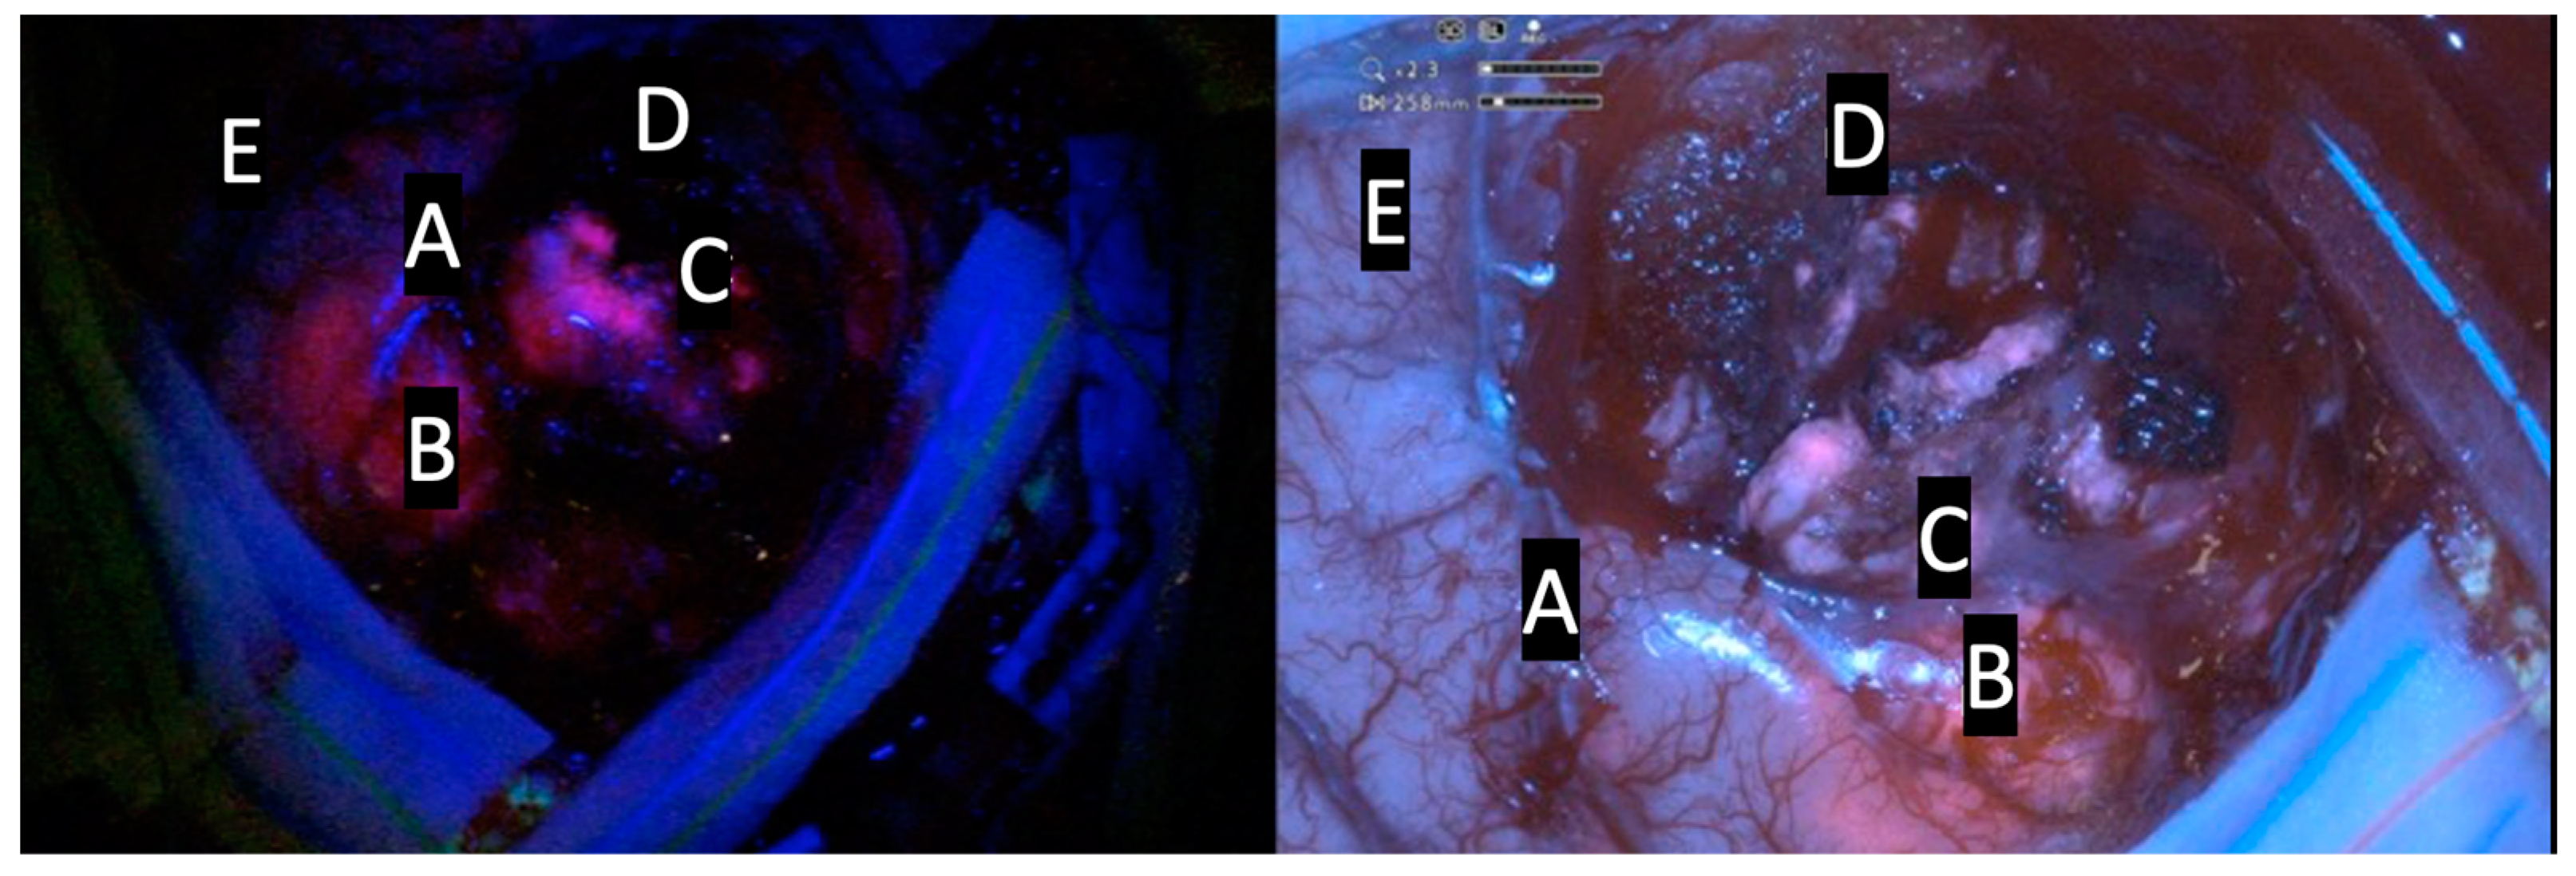

| Intensity of Fluorescence | Type of Tissue |

|---|---|

| Intense red or lava-like | Tumor |

| Faint pink or pinkish | Infiltrating tumor cells |

| Blue | Normal tissue |